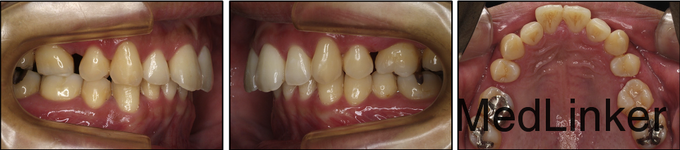

男,31岁,要求关闭牙弓内间隙

凸面型,骨性II类,青少年期拔除了3颗前磨牙但由于其他原因未继续矫正,深覆合,覆盖5.5mm,右侧磨牙I类,左侧磨牙II类关系,双侧尖牙II类